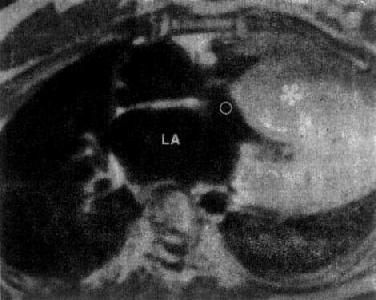

特发性心肌病

图3-2-28 特发性心肌病

心MRI,SE序列横断面图像,左心室壁及室间隔肥厚(*),LA左心房